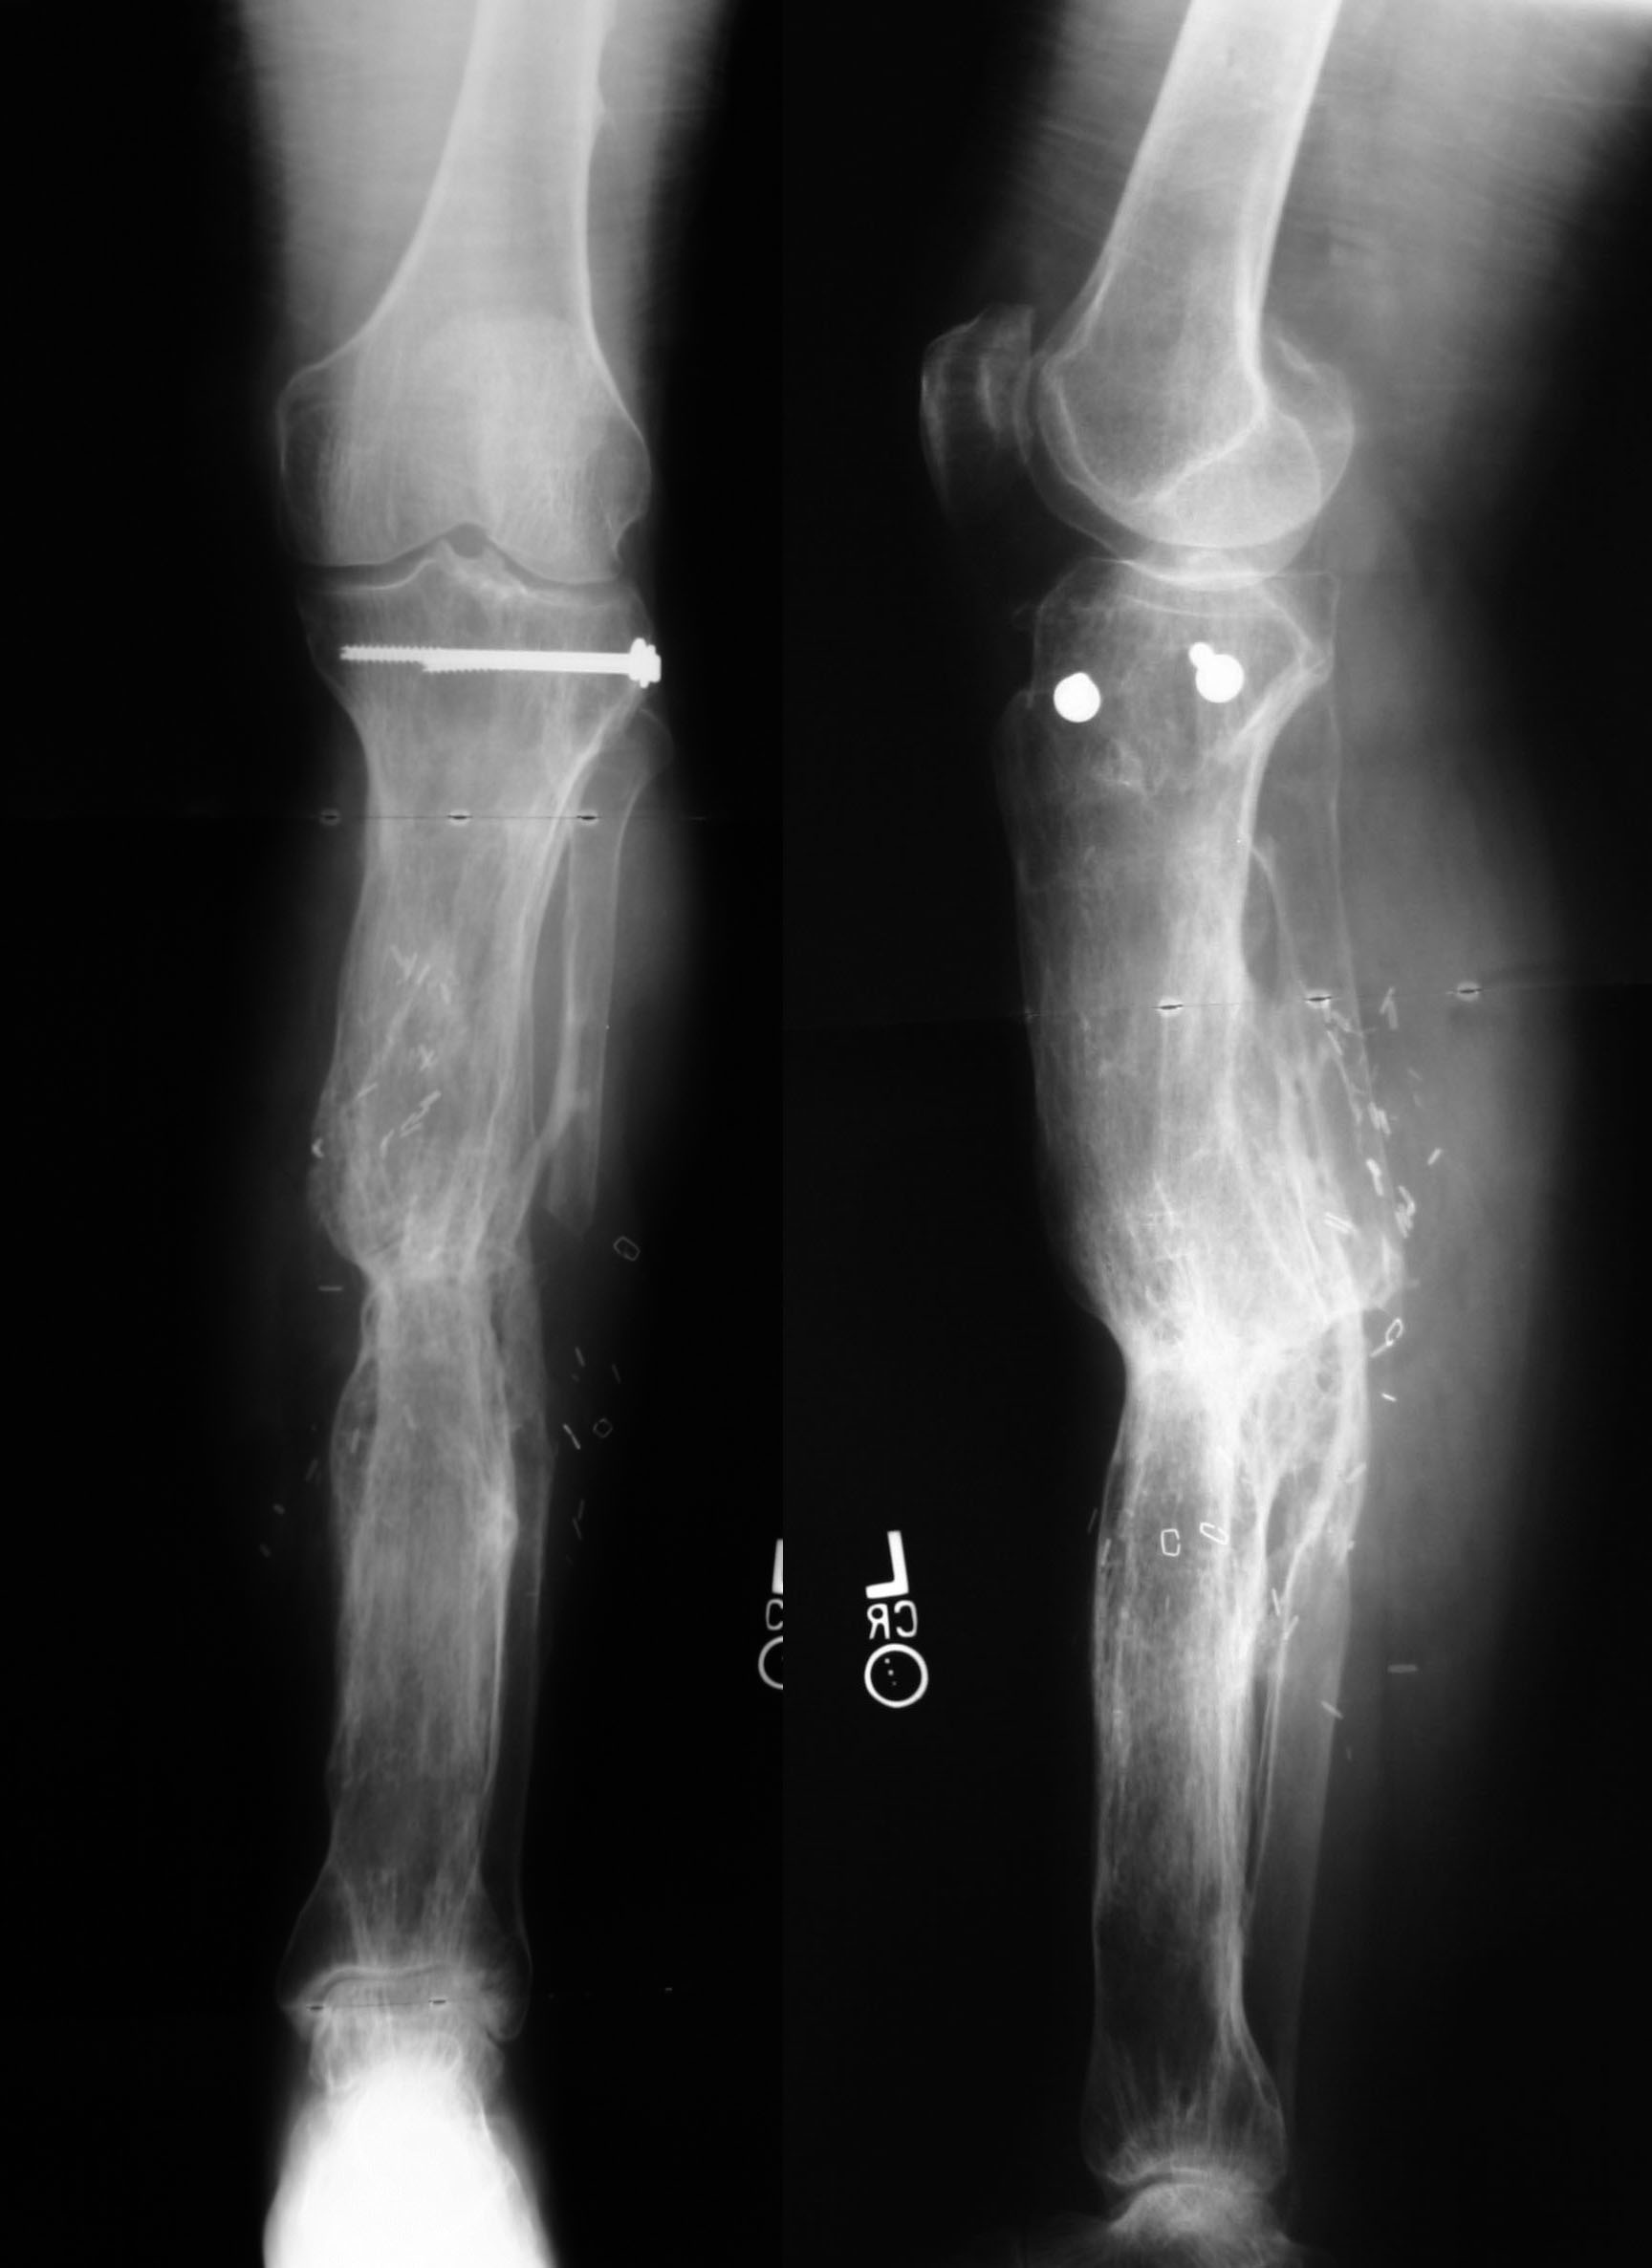

Infected Nonunion: Tibia Case 5

Treatment in ProgressFollowing aggressive debridement of infected and necrotic bone, Dr. Brinker performed Ilizarov external fixation with a double level transport. The red rectangle illustrates the bony defect; the green arrow shows the proximal corticotomy site with early new bone formation; the red arrow shows the distal corticotomy site with early new bone formation. |